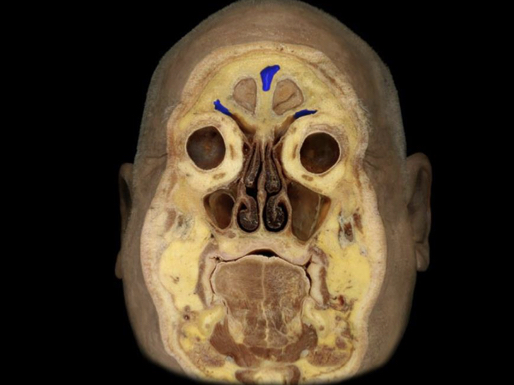

What structure is highlighted in blue?

Frontal sinus